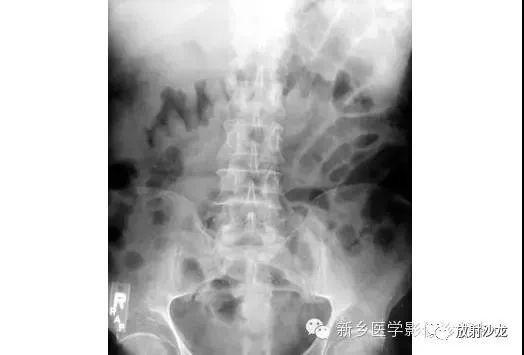

上图腹部平片检查是一6岁男孩,出现呕吐和急性右髂窝疼痛进行的。两个关键的发现在哪里?(提示:通过放射科医生所提供的箭头可以缩小关注点。)

右髂窝多个扩张的小肠襻出现小的钙化结节。小肠袢可与大肠区分开来,因为小肠的环状襞延伸至整个肠壁,而结肠袋只是部分延伸存在。在右下腹(箭头)的钙化结节高度提示阑尾粘连。这个病人开腹手术发现阑尾粘连致小肠梗阻。